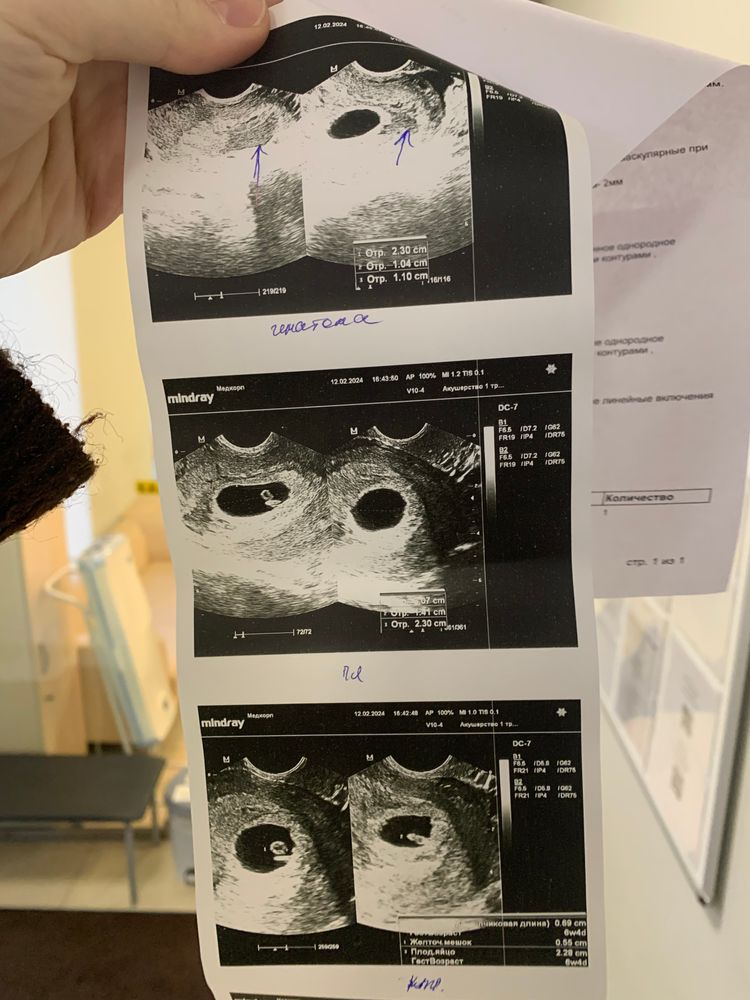

Не знаю, радоваться или нет, но нашли гематому за пя…прописали постельный режим и папаверин. Завтра повторный хгч, в пт снова прием гинеколога и повторное узи. За 4 дня мы хорошо выросли ктр с 2,8 стал 6,9. Но напугали сб всего 120 ударов в минуту… и из-за этой гематомы, она прямо за пя, пя более овальной формы…. Я получила ответы, но теперь еще страшнее… что теперь делать с этой гематомой, сколько она будет выходить, что с сб( 8-го февраля его еще не записывали, слишком маленький был), и пя какой-то формы… давление у меня 90/55 , но сердце стучит ужасно… поделитесь пожалуйста своими историями с гематомами и таким сб… впервые столкнулась